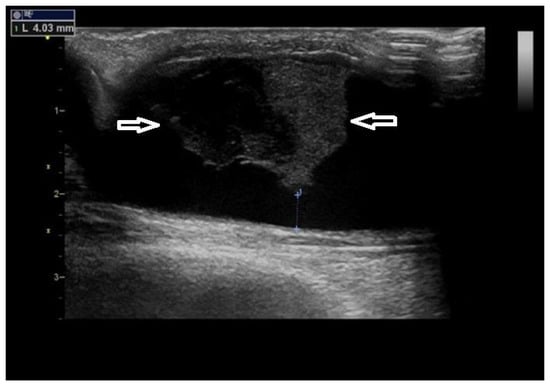

4. Predilectional Sites of Stenoses